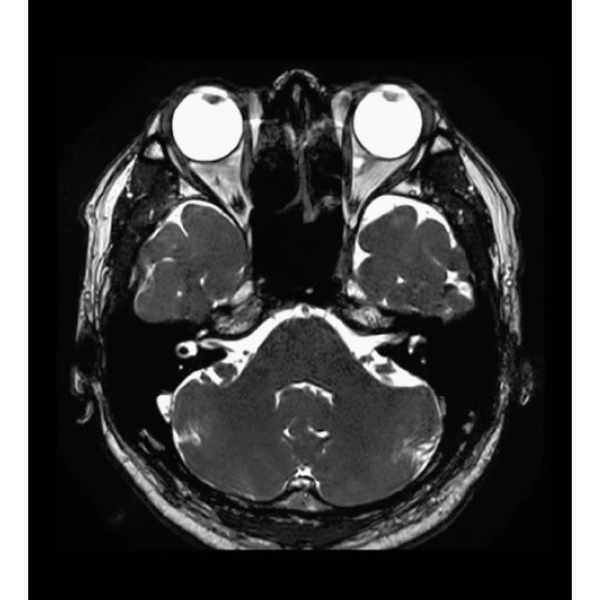

T2*WI Multi Echo,

0.38×0.38×2.0mm

0.35×0.40×3.0mm, 2:55

3D Balanced SARGE

with Phase Cycling,

0.93×0.70×1.0(0.5)mm, 1:44